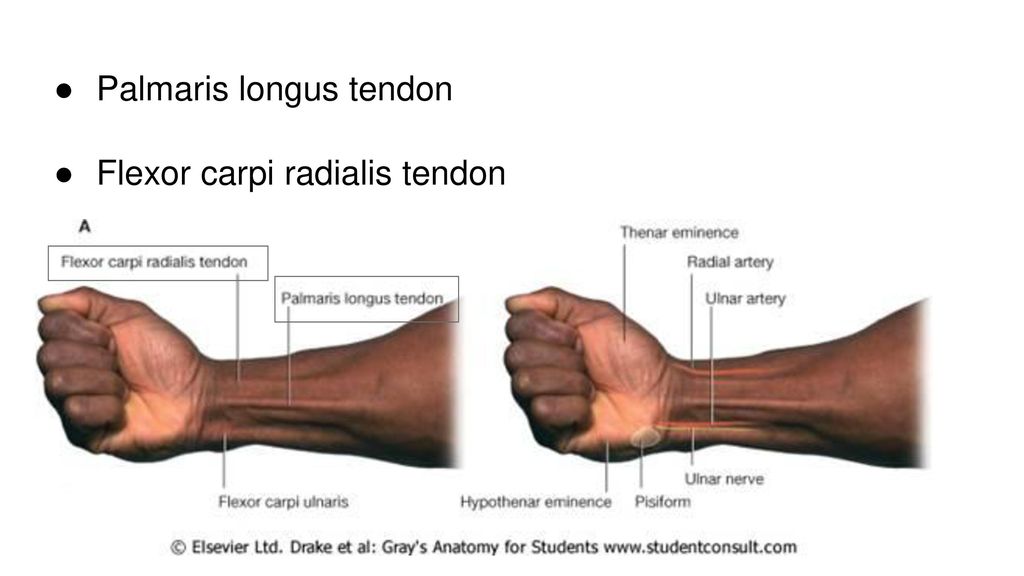

Анатомия мышцы Palmaris Longus